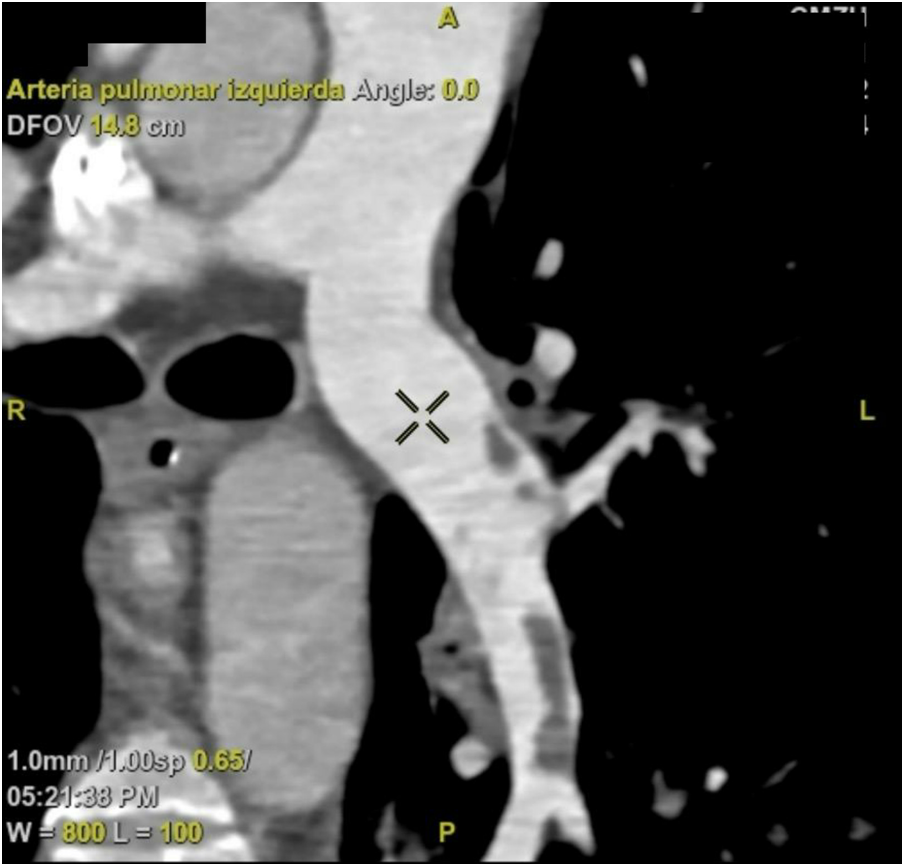

On day nine, the patient developed gram-negative pneumonia due to E. cloacae and K. pneumonia. Additionally, we switched unfractioned heparin to enoxaparin 80 mg and started intermittent hemodialysis. On the 14th day, a follow-up pulmonary CT angiography showed partial filling defects at the left pulmonary artery's main bifurcation, extending towards its segmental and subsegmental branches (Figure 4). On day 15, we started metoprolol 95 mg due to recurrent episodes of atrial fibrillation with rapid ventricular response. On the 20th day, following two unsuccessful extubation attempts, a tracheostomy was performed. On day 23, upon sedation withdrawal, we identified paraplegia, which was attributed to prolonged cardiac arrest. The neurological examination of the lower limbs showed no voluntary movement, absent deep tendon reflexes, and reduced sensation to pain and temperature with preserved proprioception and vibration. Thoracic and lumbar spine magnetic resonance imaging revealed diffuse myelitis and ischemia of the anterior horn of the spinal cord. On the 27th day, an echocardiogram showed an improved LVEF of 54%, a TAPSE of 26 mm, and absence of right ventricular dilation (31 mm).

Figure 4

CT angiography. The left pulmonary artery exhibits a partial filling defect in the segmental and subsegmental branches. CT, computed tomography.